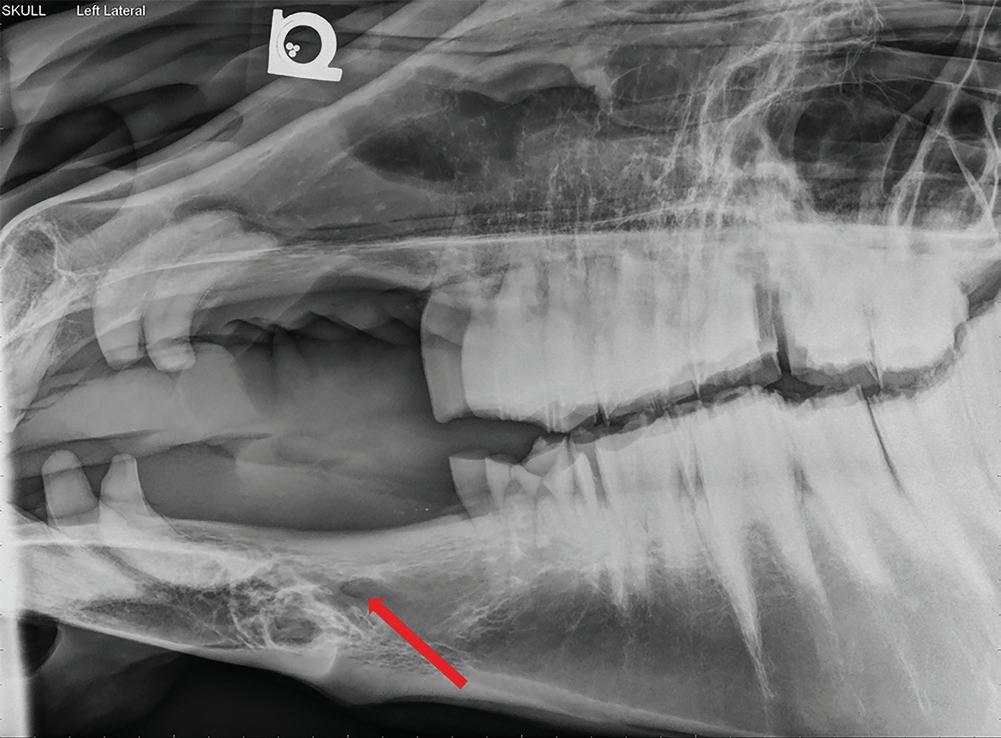

Blockade of the mental nerve at the mental foramen results in desensitization of the lower lip while advancement of a needle into the mandibular canal results in blockade of the mandibular alveolar nerve leading to desensitization of the ipsilateral incisors and premolars (Skarda et al. 2010; Rice 2017) (Figures 1.4 and 1.5). The block is achieved by elevating the depressor labii inferioris muscle and depositing

Figure 1.5 Lateral radiograph of a horse skull with severe dental disease. The mental foramen (red arrow) can be seen where the mental nerve exits to innervate the rostral aspect of the mandible. Mental nerve blockade can be used to desensitize the mandible rostral to the mental foramen to the level of the mandibular symphysis.

approximately 5 ml of local anesthetic with a 22 gauge, 1″ needle at the palpable ridge along the mandible at approximately the middle of the interdental space (Skarda et al. 2010).